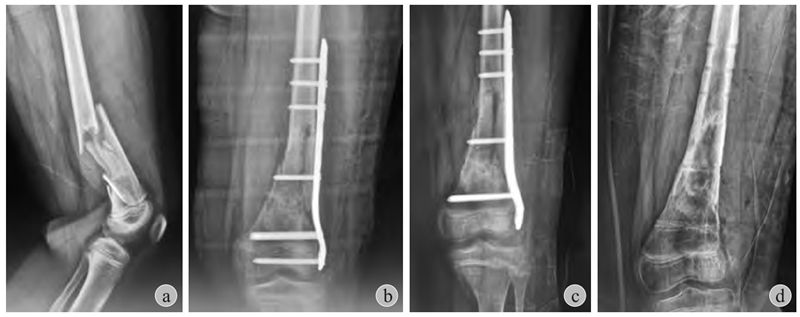

图5 患儿 男 11岁

a:左股骨远端粉碎骨折;b:切开复位+跨骺板Liss钢板固定;c、d:术后2个月虽然取出骨骺内螺钉,7个月后仍然出现膝外翻畸形